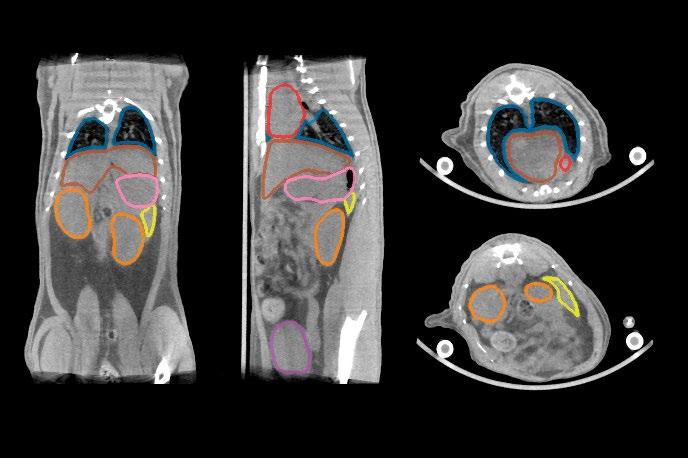

Project Title: Automated organ segmentation in preclinical MRI

The effectiveness and safety of RLT depend on accurate dosimetry, which quantifies how radiation is distributed between tumors and healthy organs. Dosimetry requires molecular imaging modalities such as PET or SPECT to track radioligand distribution, combined with anatomical imaging for reference. Manual annotation of imaging data for this purpose is highly time-consuming, making automated segmentation an essential component of modern dosimetry pipelines. Within the Cluster for Molecular Imaging (CMI), a CT-based organ segmentation model already reduces annotation time from nearly an hour to just a few minutes while maintaining high accuracy.

CT provides reliable anatomical information but has limited soft-tissue contrast. MRI offers much better visualization of soft tissues and therefore has the potential to improve organ segmentation quality in preclinical studies. However, annotated MRI datasets are scarce, and models trained on CT do not transfer easily to MRI.

This project will address these challenges by developing an organ segmentation framework for preclinical MRI. The student(s) will curate and annotate an MRI dataset, adapt the existing CT-based nnU-Net model2 through transfer learning, and explore strategies such as cross-modality fine-tuning, contrastive representation learning, or synthetic data generation3. Performance will be evaluated in terms of segmentation accuracy, robustness across imaging conditions, and usability within CMI’s automated dosimetry pipeline. The results will clarify the role of MRI as a complementary or alternative modality to CT for automated organ segmentation in RLT research.

LEFT: AUTOMATICALLY SEGMENTED ADULT MICE USING THE CURRENT CMI PIPELINE FOR CT

RIGHT: MANUALLY SEGMENTED ADULT MOUSE T1-WEIGHTED MRI - SCAN